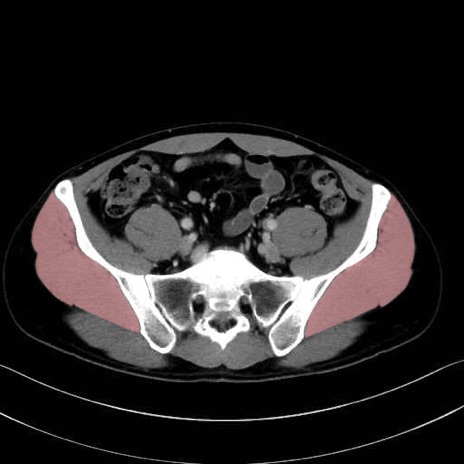

1. 体幹部(腹部・背部・後腹壁)の筋肉

2. 腸腰筋群と骨盤底筋

大腰筋 (Psoas major)

腸骨筋 (Iliacus)